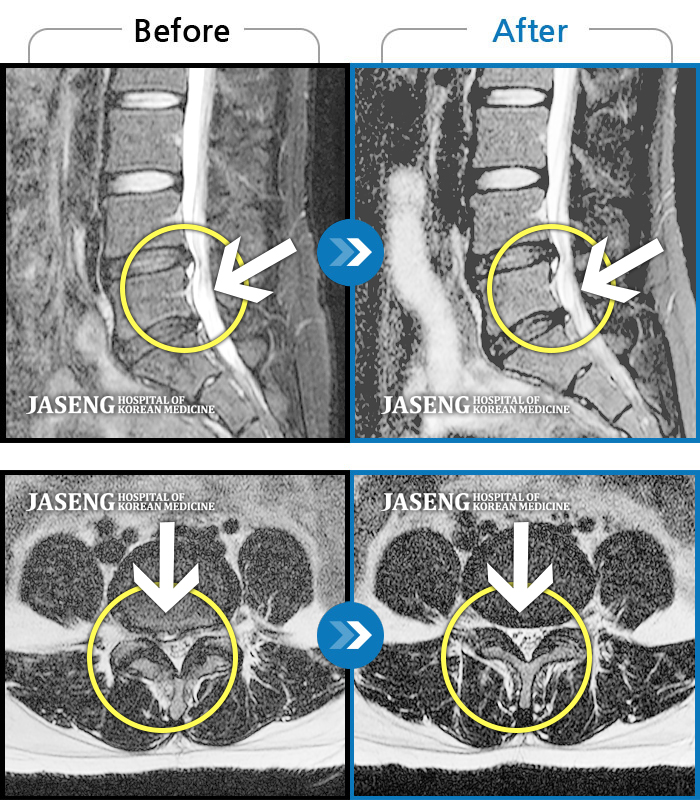

허리디스크

인천 · 강아현 원장

물건을 들다 삐끗한 후 발생한 허리 통증 및 하지 방사통, 하지 감각 저하 및 근력 저하 발생

촬영시기

2025.03.04 ~ 2025.09.10

2025.09.22